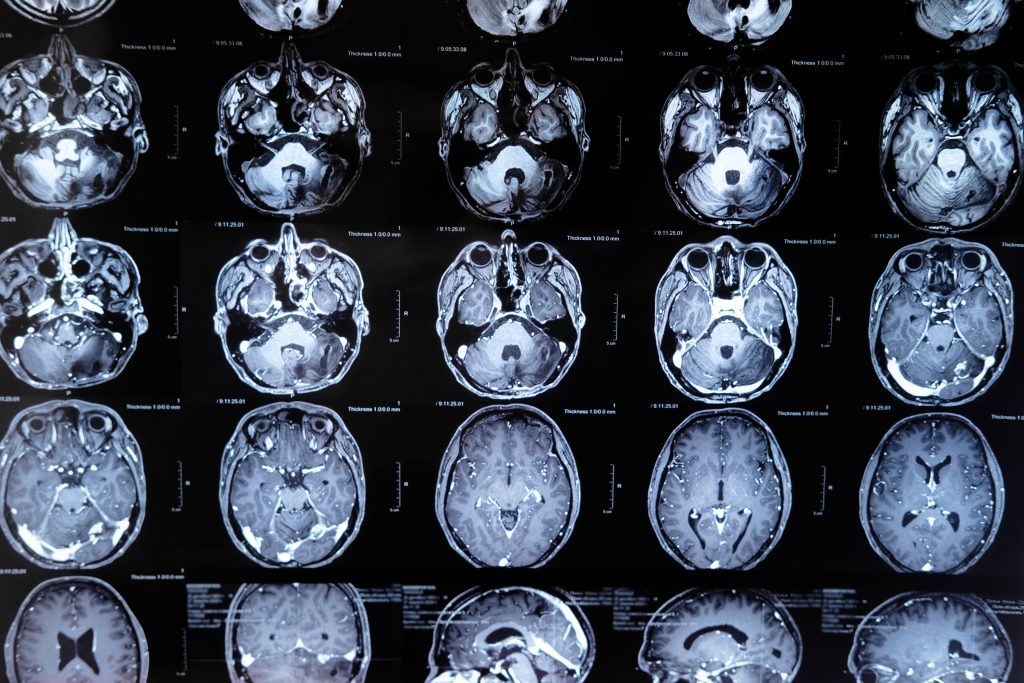

Imagens diagnósticas rápidas

- Os exames de imagem, como a tomografia computadorizada (TC) ou a ressonância magnética (RM), são fundamentais para confirmar o diagnóstico de um acidente vascular cerebral e determinar a extensão do dano cerebral.

- A rapidez com que esses exames são realizados pode influenciar na escolha do tratamento e em sua efetividade.